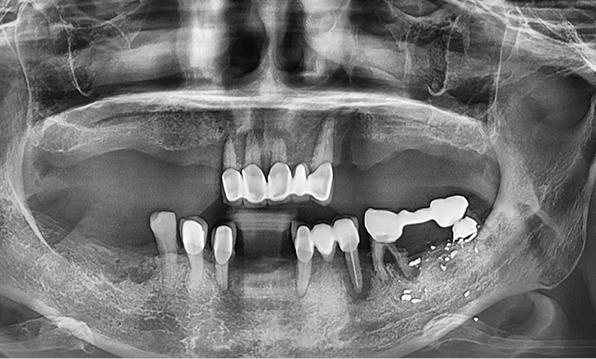

Case 04

Before After